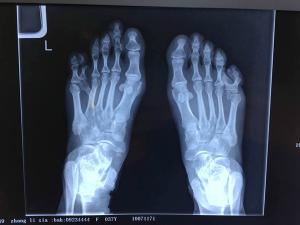

原來,她的雙腳天生就有六趾,「我長到現在37歲了,沒有在外人面前露過腳,就連自己的兩個孩子也沒見過我光腳。」

原本,阿娟是打算跟六趾和平共處的,不料右腳那個多出來的腳趾頭很不安分,一點點往上翹起來,令她走路都受影響。這反倒逼阿娟下了決心:把多出來的腳趾頭給割了。

杭州市三醫院骨科的趙琦輝醫生指:「多趾/指畸形是嬰兒出生時最常見的異常情況,通常與遺傳或是環境汙染相關,尤其是母親在懷孕4~8周期間,如果發生病毒性感冒或是接觸了射線或是吃了某些藥物等,都可能導致胎兒腳趾或是手指的畸形。而對於此類畸形,保守治療沒有任何效果,唯一的辦法就是手術切除。但考慮到太早手術可能會影響孩子骨骼發育,因此建議孩子到10多歲發育完成後再手術比較適宜。」